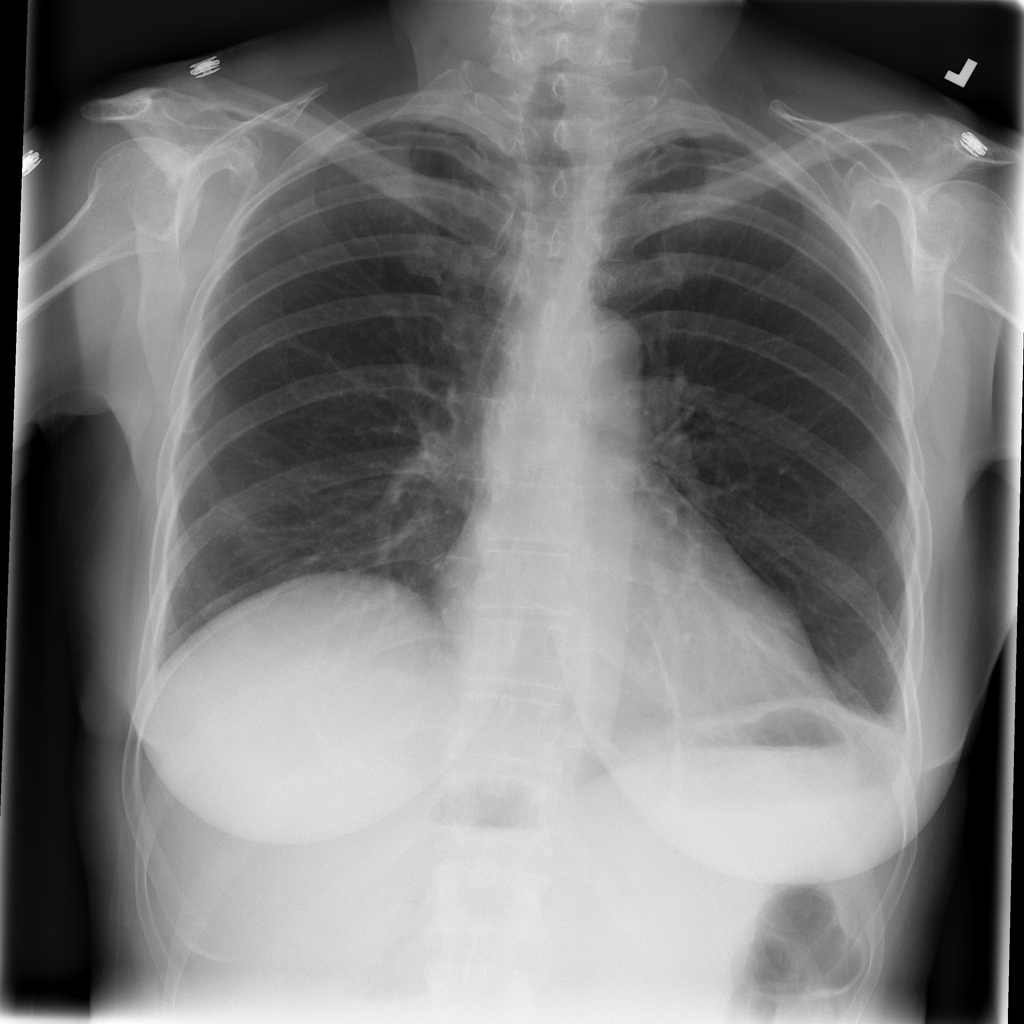

PAT-BA30 · IMG-001Atelectasis

PAT-BA30 · IMG-001

PA